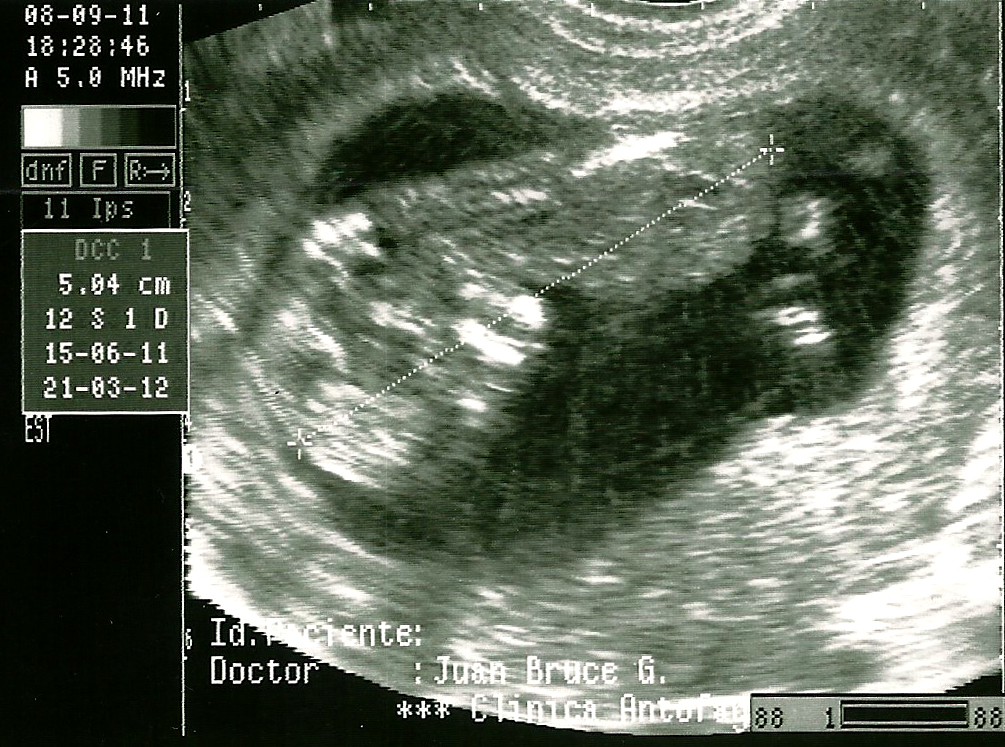

Muchas gracias chiquillos. Bueno sigo mostrando avances de mi proyecto anexo.vengo de la clínica y ya tengo la eco de las 12 semanas, todo perfecto, vi cómo se movía con sus manitos, piecesitos, ya tiene facciones, es una emoción increíble.

Estaba parado frente al doctor mientras veíamos al bebe en la pantalla de la ecografía, sabía que apretando un botón tira la imagen, es decir para mí era como apretar el botón render, entonces no podía estar tranquilo viendo que cuando estaba justo por apretar la imagen iba a salir mal, entonces le decía, a ver doctor, cuadremos un poco la imagen y enfoquemos mejor, que la que piensa imprimir está muy pixelada Vaya, mi mujer me miraba con cara de, esta si que está cagada de la cabeza.